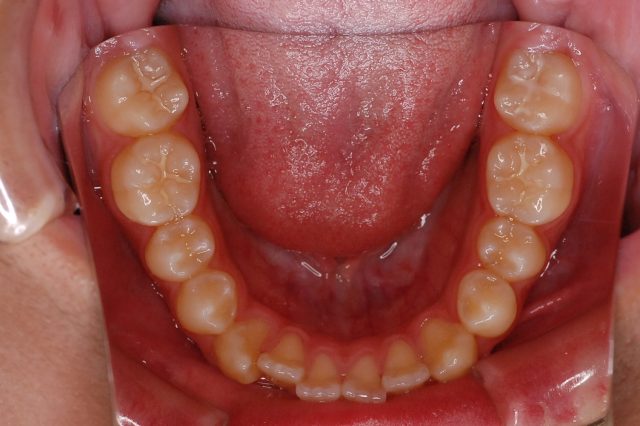

Before

After

主訴

前歯で噛めない

治療期間・回数

2年6ヶ月・30回

治療方法

マルチブラケットにて上下左右4本抜歯

費用

850000+税

デメリット・注意点

歯根吸収 歯肉退縮